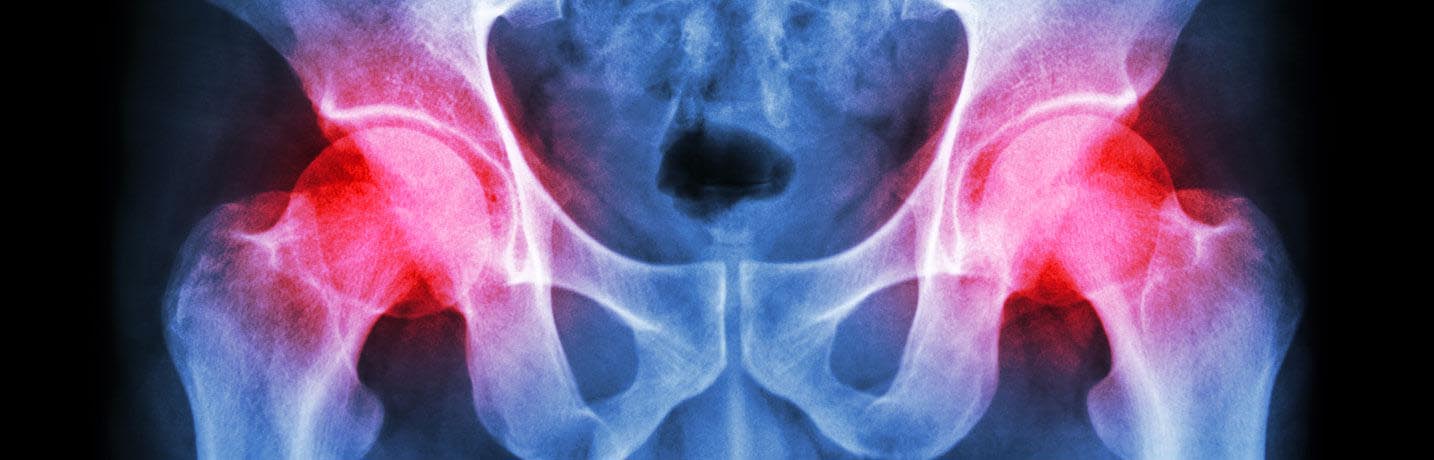

La hanche est l’une des plus grosses articulations portantes du corps. C’est une articulation sphéroïde ce qui veut dire qu’elle a la forme d’une boule (la tête) qui s’emboîte dans une cavité. Une arthroplastie complète de la hanche est une opération visant à remplacer la tête qui se situe tout en haut de l’os de la cuisse (fémur) et la cavité de la hanche.

On pratique habituellement une arthroplastie totale de la hanche en cas de douleur aiguë et de perte de fonction de stade avancé et quand les autres traitements ne soulagent plus la douleur. Une hanche peut également être remplacée en cas de fracture.